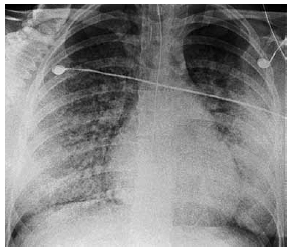

Mulher de 53 anos de idade, etilista, apresenta quadro de vômitos intensos há 2 dias, com provável aspiração orotraqueal. Em seguida, evolui com dispneia intensa, agitação, confusão e cianose de extremidades. Exame clínico: PA: 115 x 65 mmHg, FC: 128 bpm, FR: 44 ipm, T: 36,3 ºC, e SatO2: 54%; ausculta pulmonar com roncos e estertores difusos. A radiografia realizada é mostrada a seguir.

Com esses dados, a hipótese diagnóstica mais provável é de